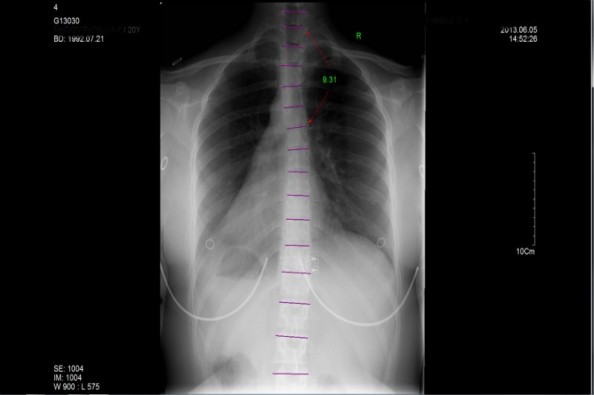

Recently after finally getting my chance to go see a chiropractor and get some X rays done was when I realized how bad the damage was. The news I got back was that I'm doing pretty badly, which for someone who needs to sew to make a livelihood is a terrible thing to find out.

I knew it was bad from simply not being able to function without pain everyday, but these X rays really made it real for me. I was told very honestly that I don't have a lot of time before this gets more critical than it already is, and frankly I can barely get through the day anymore without searing pain in my back, to the point of maybe not being able to finish school.

The prognosis is that if I wait longer, the bones have a risk of fusing together in the wrong position, and causing much more serious heath issues that threaten to do a lot worse than just cause me pain.

Below you see the x ray images I received back showing the damage.